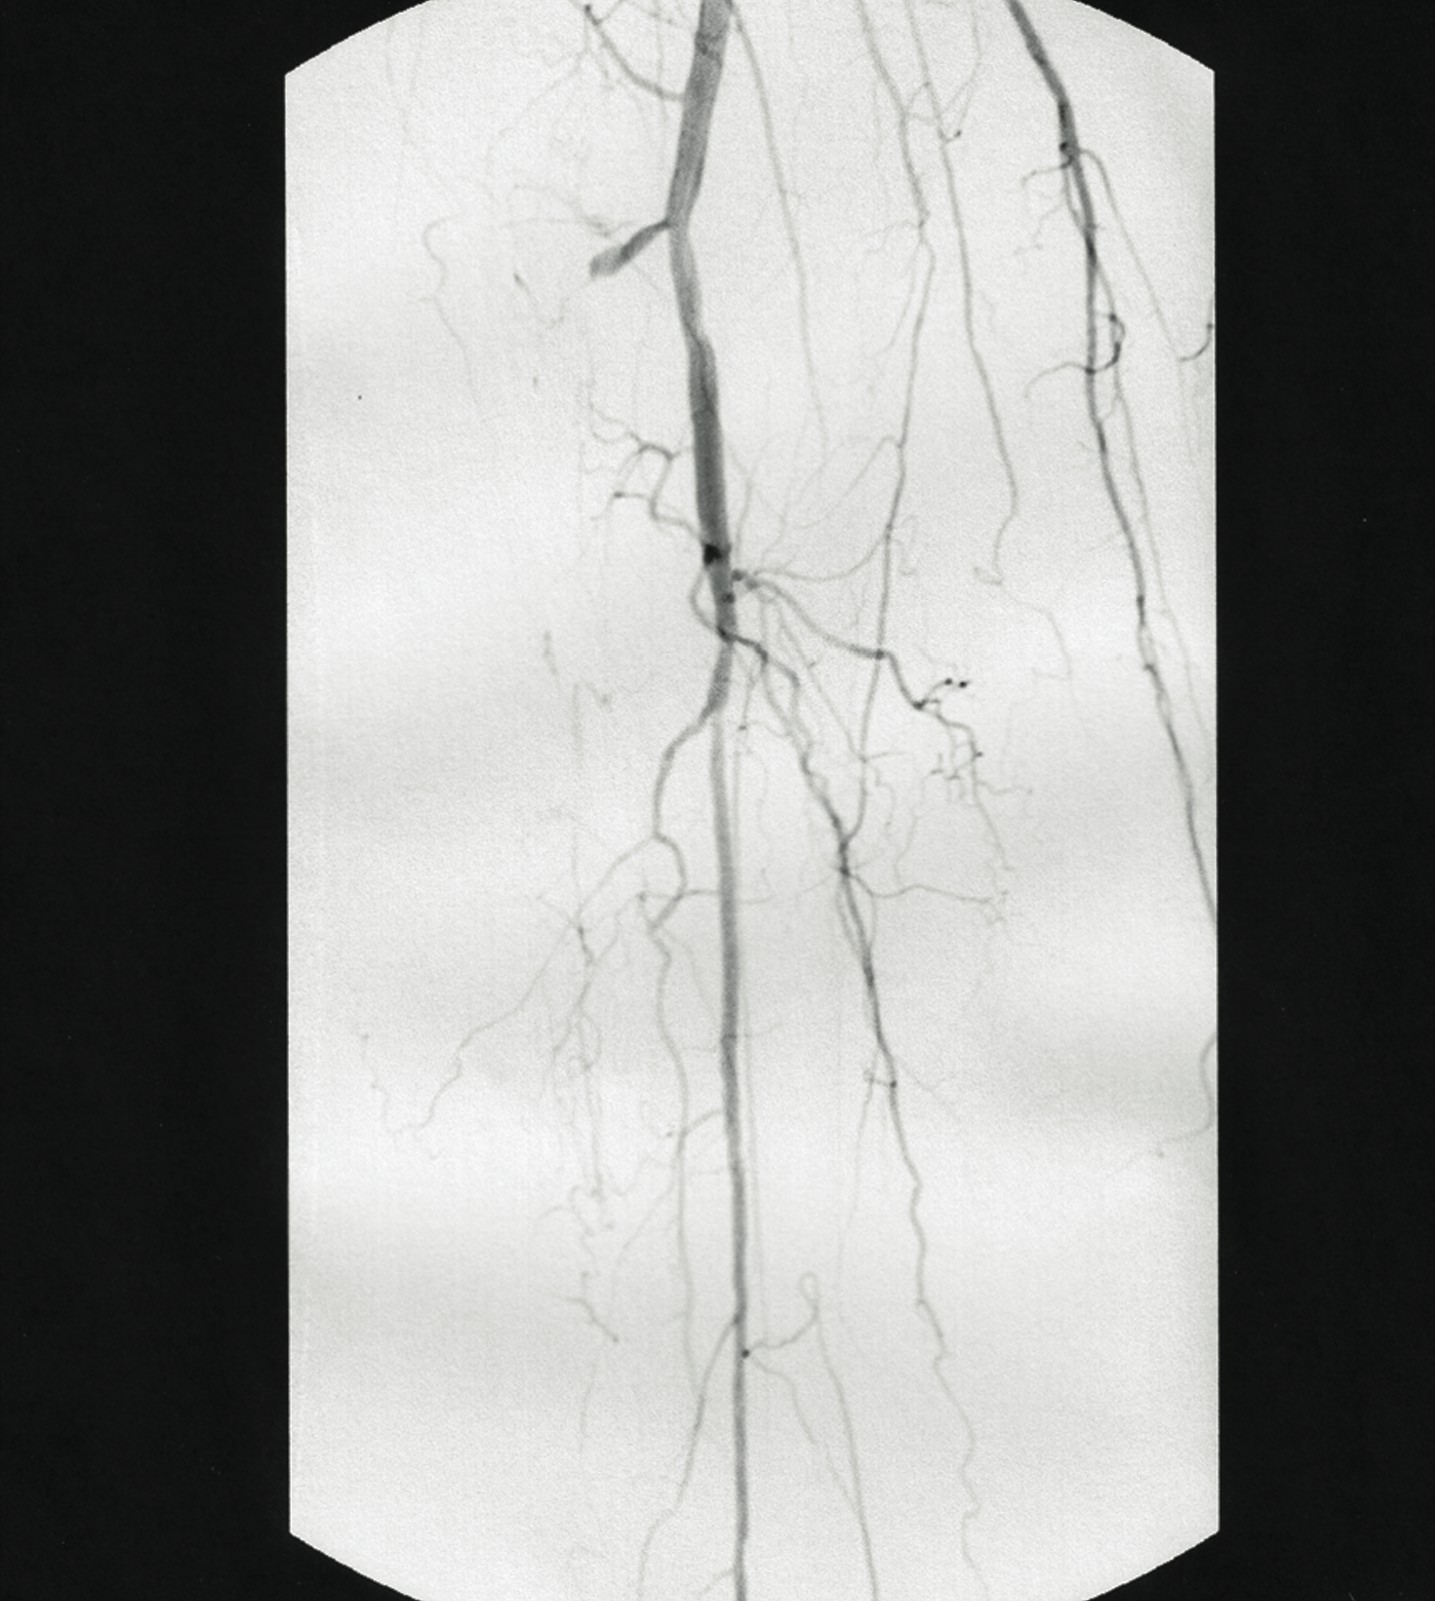

In one case study, a 69-year-old male was referred to a lower extremity limb salvage clinic with severe painful claudication and ulceration. He had prior amputation of the hallux and second digit of the right foot secondary to gangrene, and a prior endovascular angioplasty of the anterior tibial artery. He was scheduled for a below-knee amputation at another facility. His past medical history included diabetes mellitus for eight years, hypertensive cardiovascular disease and chronic renal failure, which initially required dialysis and eventually led to a right orthotopic kidney transplant. The patient history also included monocular blindness in the right eye. The patient was a former smoker who quit 30 years ago. His family history was significant for diabetes mellitus maternally and morbid obesity. He did have night cramps and reproducible leg pain with ambulation. His medications included Medrol, Cellcept, Prograf, Avandia, Zocor, Ambien, Atenolol, aspirin and insulin. He denied any known allergies. In regard to the physical exam, the patient’s vital signs were stable. His blood pressure was 137/84, his pulse was 80, respirations were 14 and his temperature was 98.5ºF. His pain was seven out of 10 on the visual analogue scale (VAS). His random blood sugar (RBS) at three hours postprandial was 131 mg/dL. The vascular exam revealed non-palpable pulses to the right lower extremity. The title= After delivering the catheter to the lesion, one would position it at the selected treatment area and switch the driver on. Switching the driver on automatically deflects the catheter tip, lifts the cutter and activates the motor. Doppler exam revealed a non-Dopplerable posterior tibial artery and a weakly monophasic dorsalis pedis artery. The distal foot was cool to the touch with elevated capillary refill time. An open ulcer was present at the prior amputation site of the first and second digits with gangrenous changes present. His right ankle-brachial index (ABI) was 0.69. Previous vascular intervention results included a balloon angioplasty of the right anterior tibial artery. His prior angiogram revealed a 100 percent occlusion of the posterior tibial artery and 75 percent stenosis of the proximal anterior tibial and fibular arteries. We referred the patient to a cardiovascular interventionalist for immediate vascular evaluation. The patient underwent a selective abdominal aortogram, which revealed severe infrapopliteal disease bilaterally. The posterior and anterior tibial arteries are 100 percent occluded proximally. The peroneal artery was patent and supplied collateral arterial circulation to the distal anterior and posterior tibial arteries. The patient underwent endovascular intervention including laser atherectomy, Silverhawk endovascular atherectomy and balloon angioplasty of the anterior tibial artery. The patient required a transmetatarsal amputation (TMA) after the Silverhawk procedure but avoided the need for a significant proximal amputation. There were no complications while healing the TMA. He exhibited no further complications 12 months after the endoscopic atherectomy.